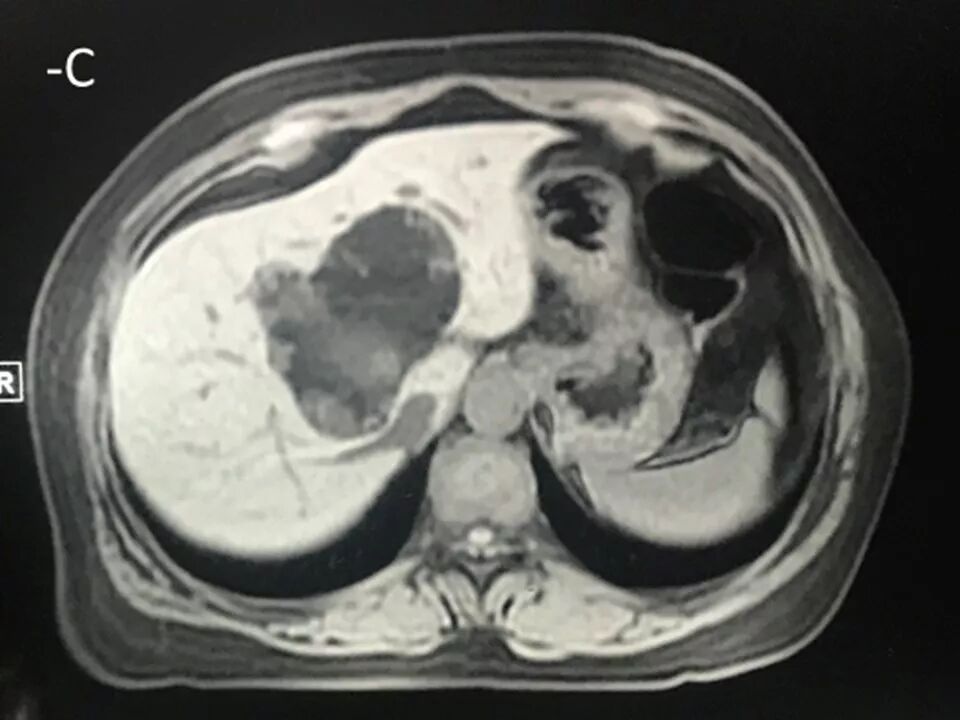

MRI表现:

肝内单发占位灶,累及肝左右叶及尾叶。T1WI示病灶以低信号为主,边缘多枚等信号结节,正反相位未见明显脂肪成份;T2WI示病灶以粘液成份为主呈高信号,边缘多枚稍高信号结节(相对肝实质),DWI呈不均匀等高信号,ADC图以高信号为主。动脉期病灶边缘均匀强化,壁结节显著强化,门脉期边缘仍持续强化,边缘光滑,壁结节呈相对等低信号。MRCP示胆管扩张,病灶与胆管相通。